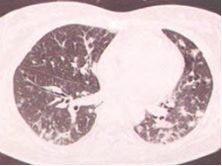

3. 肺泡间质型

双肺磨玻璃影或条索状阴影,可伴有支气管血管束增粗弥漫网格影,伴支气管扩张症。